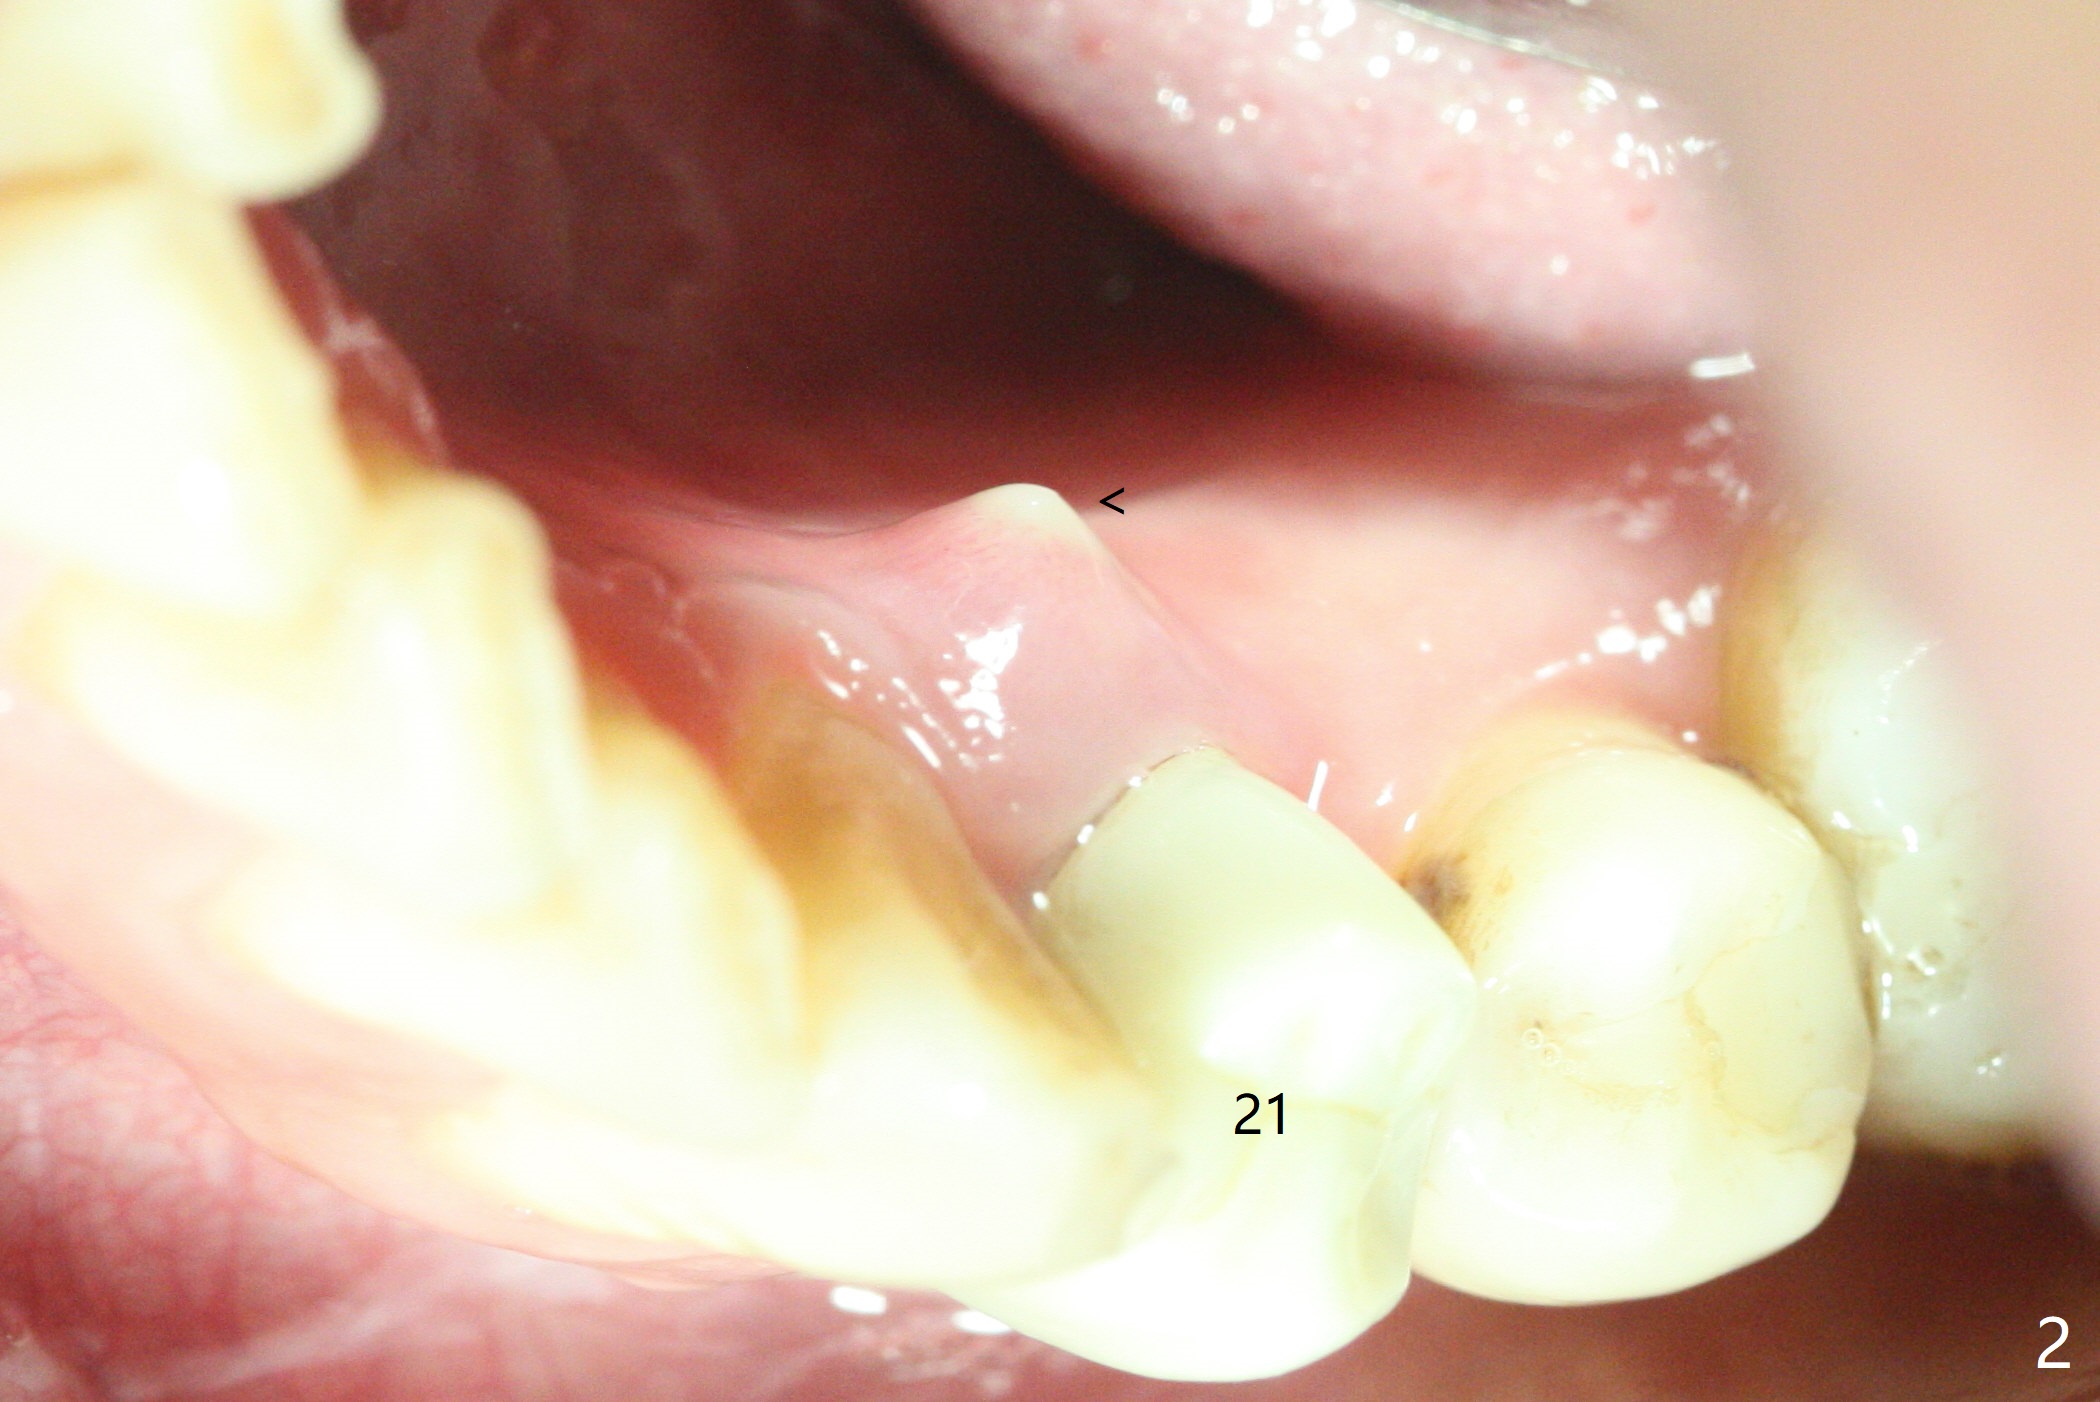

A 42-year-old man has been our patient for 3-4 years (Fig.1). An asymptomatic fistula develops lingual to the tooth #21 (Fig.2). An oblique fracture line appears to be next to a post (Fig.3 ^). A 3.5x11.5 mm implant seems to be able to be placed immediately lingual to the thick lingual plate with guide (Fig.4 L). No buccal deviation will occur with sufficient buccal gap. Design of an immediate implant at #21 (coronal section, Fig.5). In fact the root remains in place first (i.e., extract the crown first, Fig.5'). When osteotomy is done with the last drill 4x11.5 mm, there will be no deviation because of even counteraction between the buccal root and the lingual plate (Fig.6'). Then the root will be removed. But the 4.5x11.5 mm implant may be deviated buccal because of implant engagement into the lingual plate without buccal counteraction. Therefore, a 4x13 mm implant will be placed following 3.5x13 mm (last) drill. The implant is placed between the mesial and distal walls (Fig.7 sagittal section).